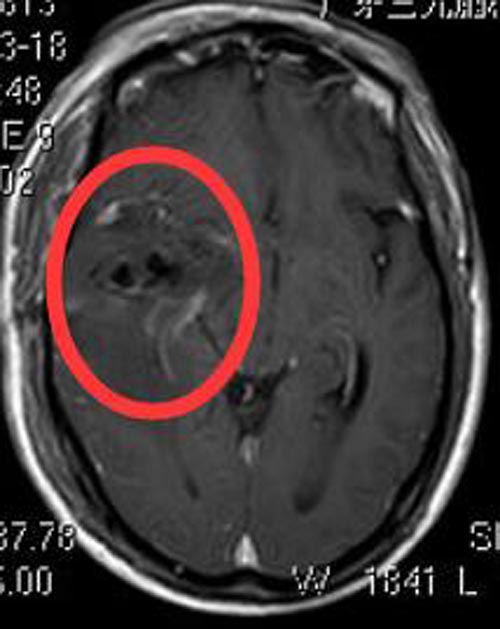

术前常规检查后,由综合神经外科鲁明主任主刀,在全麻下行右侧颞叶巨大占位切除术,术中皮层电生理监测示颞中回局部异常放电,导航定位下切除部分颞中回及颞下回脑组织,显微镜下深部见病变组织,呈灰褐色,质软,边界不清,血供丰富,予镜下分块切除,手术顺利。已康复出院。病理结果回报:胶质母细胞瘤 IV级。

▲术后